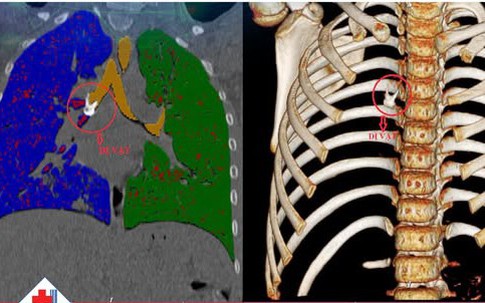

Kịp thời cứu sống bé sơ sinh mắc tim bẩm sinh phức tạp nhờ phát hiện từ trong bào thai

Mẹ và béGĐXH - Nhờ được phát hiện sớm từ giai đoạn bào thai nên các bác sĩ đã lập kế hoạch sinh, huy động đội ngũ can thiệp tim mạch tại chỗ cho em bé ngay khi chào đời.